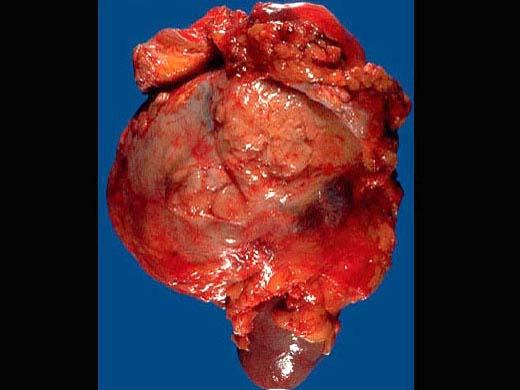

问题 男性,45岁。B超发现左肾肿物2个月。考虑为肾脏肿瘤,行左肾切除术,患肾大体如图所示,镜检如图所示,正确诊断为 ( )

选项 A.左肾透明细胞癌Ⅰ级 B.左肾细胞癌(肉瘤样型) C.左肾颗粒细胞癌 D.左肾乳头状腺癌 E.左肾梭形细胞癌

答案 A